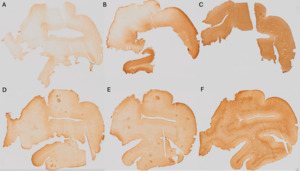

Pale=0 (Figure 1A); Heterogeneous=1 (Figure 1B); Dark=2 (Figure 1C).

No contrast=0 (Figure 1D); Blurred contrast=1 (Figure 1E); Sharp contrast=2 (Figure 1F).

A collage of images of a person's body AI-generated content may be incorrect.

Figure 1.Criteria for assessment of the histology quality variable.

Staining intensity showing A) Pale section=0; B) Heterogeneous section=1 and C) Dark section=2. GM-WM contrast showing D) No contrast=0; E) Blurred contrast=1 and F) Sharp contrast=2. These sections come from the right occipital block fixed with SSS.